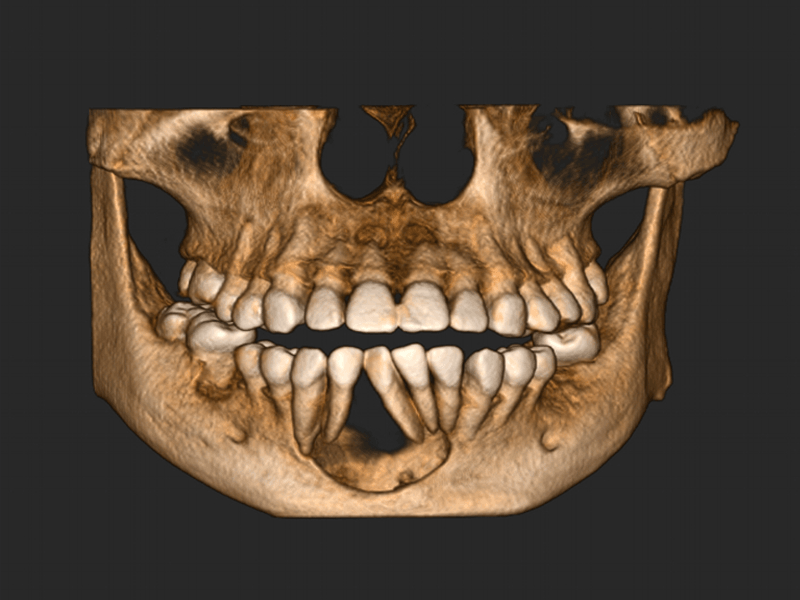

Pro Patient: Our state-of-the-art cone-beam computed tomography (CBCT) technology could selectively image the sinus, oral maxillofacial, para-nasal sinuses, ear & throat regions.

3D Imaging with Field of View sizes available in:

Proactive Dental Management thru our 3D Imaging Manipulation Software

With Oral Maxillofacial CT Scans, your dentist enhances his ability to proactively manage your health concern thru accurate diagnosis & better treatment planning. Moreover, the patient benefits from a painless,low radiation dose CT Scan procedure.